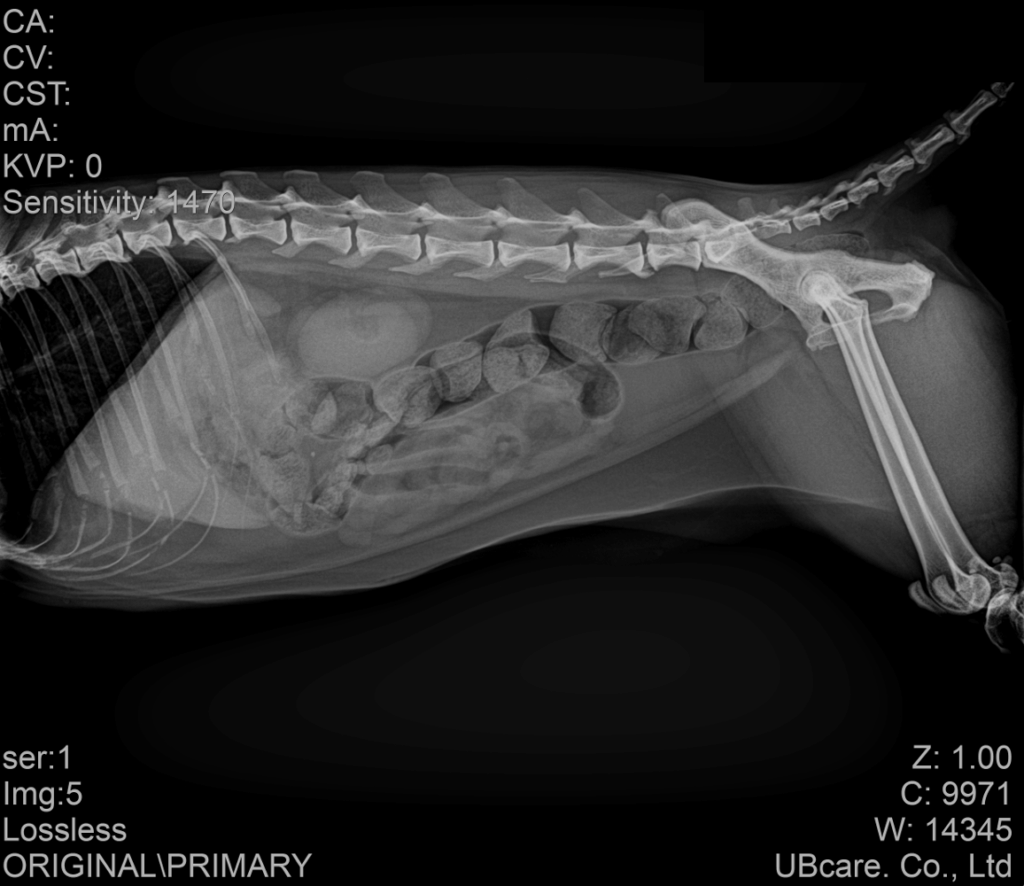

이에 따라 혈액검사와 방사선 검사, 복부 초음파 검사를 포함한 전반적인 평가를 진행하였습니다. 혈액검사에서는 췌장염 지표인 fPL이 양성으로 확인되었고, 간 수치도 함께 증가되어 있었습니다. 방사선 검사에서는 장폐색이나 명확한 이물 소견은 보이지 않았지만 대변 정체가 일부 확인되었습니다.

내원당시 복부방사선검사 결과 / 출처: 강서YD 동물의료센터